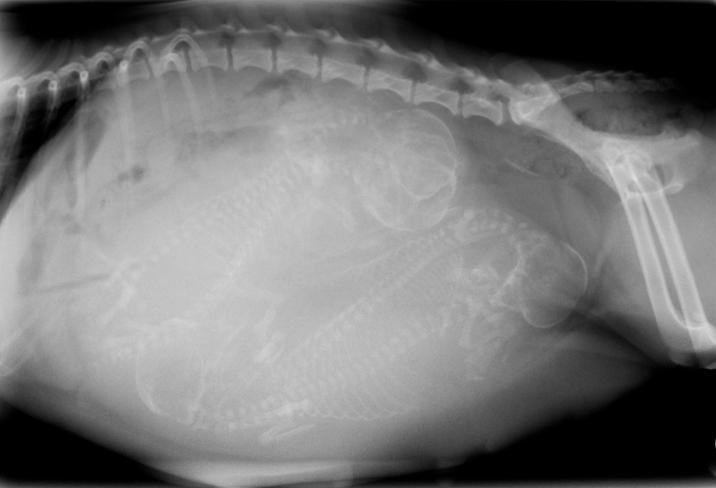

Los fármacos, concretamente hormonas que deben ser siempre prescritas por el veterinario, pueden utilizarse para interrumpir el embarazo aproximadamente hasta los 45 días de gestación. En ocasiones presentan efectos secundarios. Si el embarazo es temprano se absorben los fetos pero si ya está avanzado la perra tendrá que expulsarlos, lo que va a equivaler a un parto con todos los riesgos que pueden darse en este proceso como obstrucciones e incluso cesárea.

Cómo interrumpir el embarazo de una perrita pasa también por su esterilización. Teóricamente podría hacerse en cualquier momento pero suele depender del veterinario, ya que también entran en juego aspectos morales. Lo que es cierto es que cuánto más avanzado esté el embarazo más arriesgado es intervenir por la acumulación de sangre en la zona, el crecimiento del útero, etc. Y habría que valorar si concurre en la perra algún factor que desaconseje la intervención.